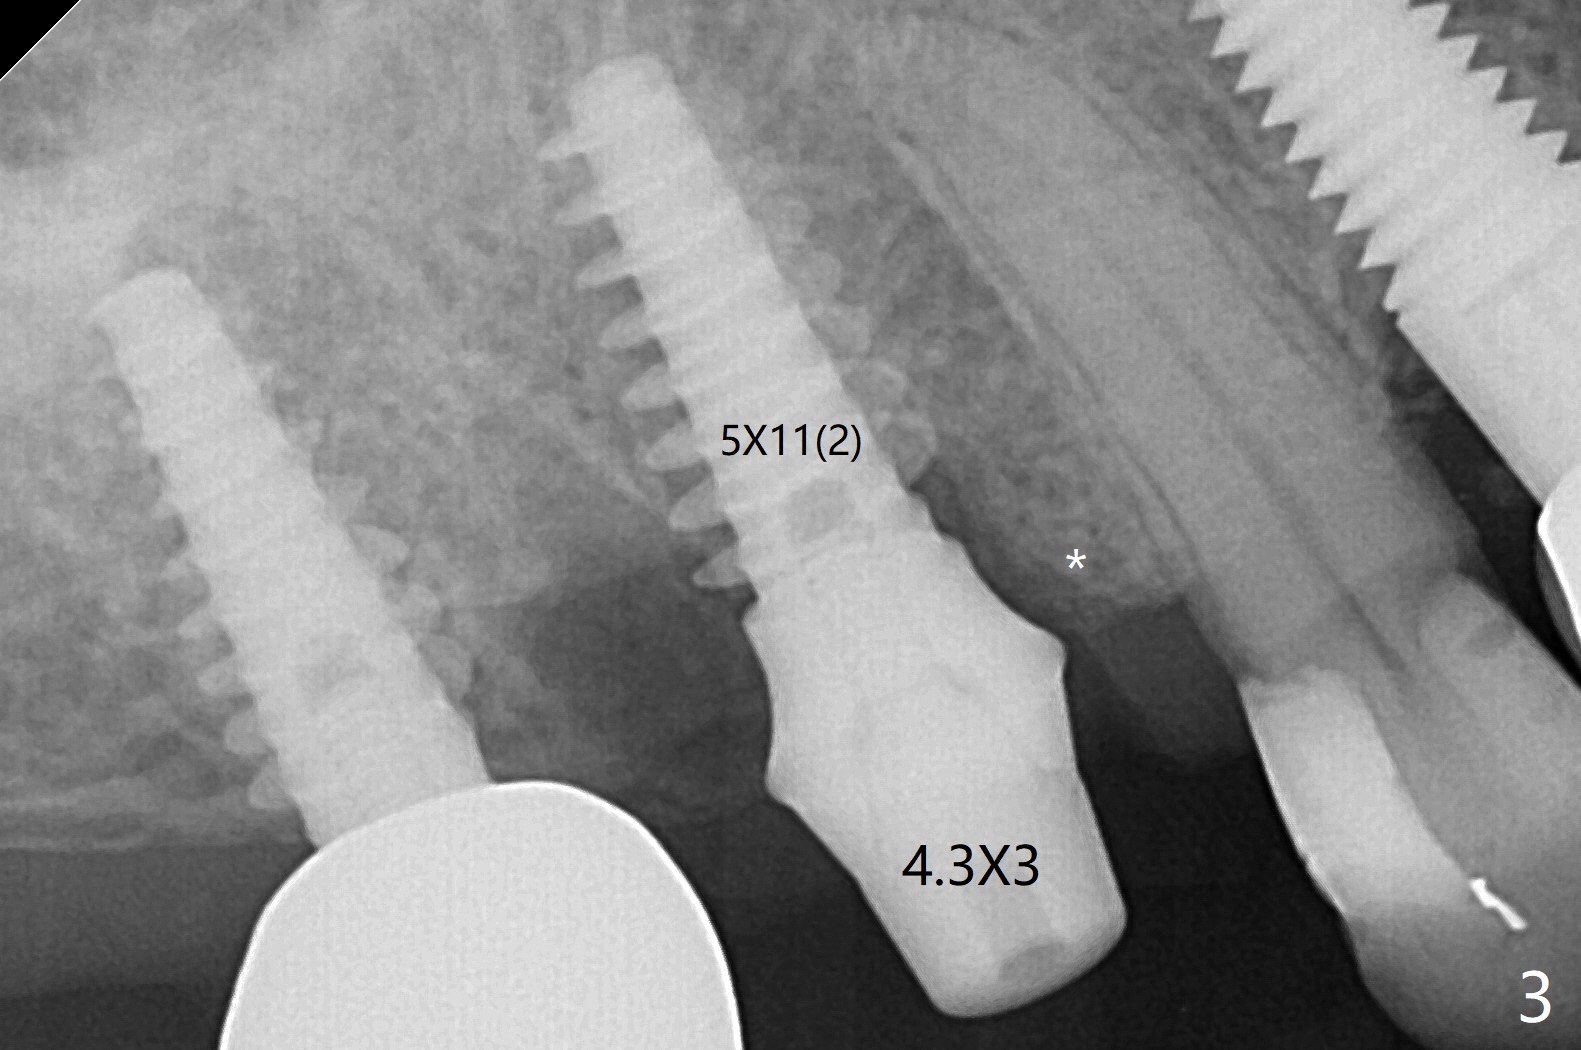

右上6拔牙困难,需要分根。3毫米补偿磨平钻头不能接触尖细中隔,即使使用外科手机和钻头,在导板指引下,尖钻头没有在中隔(S)打洞,使用2.2x7.3毫米钻头后,发现钻洞在近中颊侧窝。用过大一号钻头后,拍摄根尖片,方位偏差不大(图一,二),所以继续钻洞,钻头直径小0.5毫米,放置IS报废4.5乘10毫米植体,稳定性可以,也放置IS准基台(5.2x3毫米)。放置5x11(2)毫米Magicore(~20 Ncm),好像太接近近中牙槽骨(图三:*)。即刻放置4.3x3毫米实心基台。胶原塞放置远中颊侧和腭侧牙槽窝后,骨粉不仅覆盖刚植入的植体螺纹,而且推往7近中(图四:*(事先需要去除那里软组织,与图一比较))。其实可以先徒手用尖钻头在尖细中隔开始钻洞,为后来导板钻洞引导。